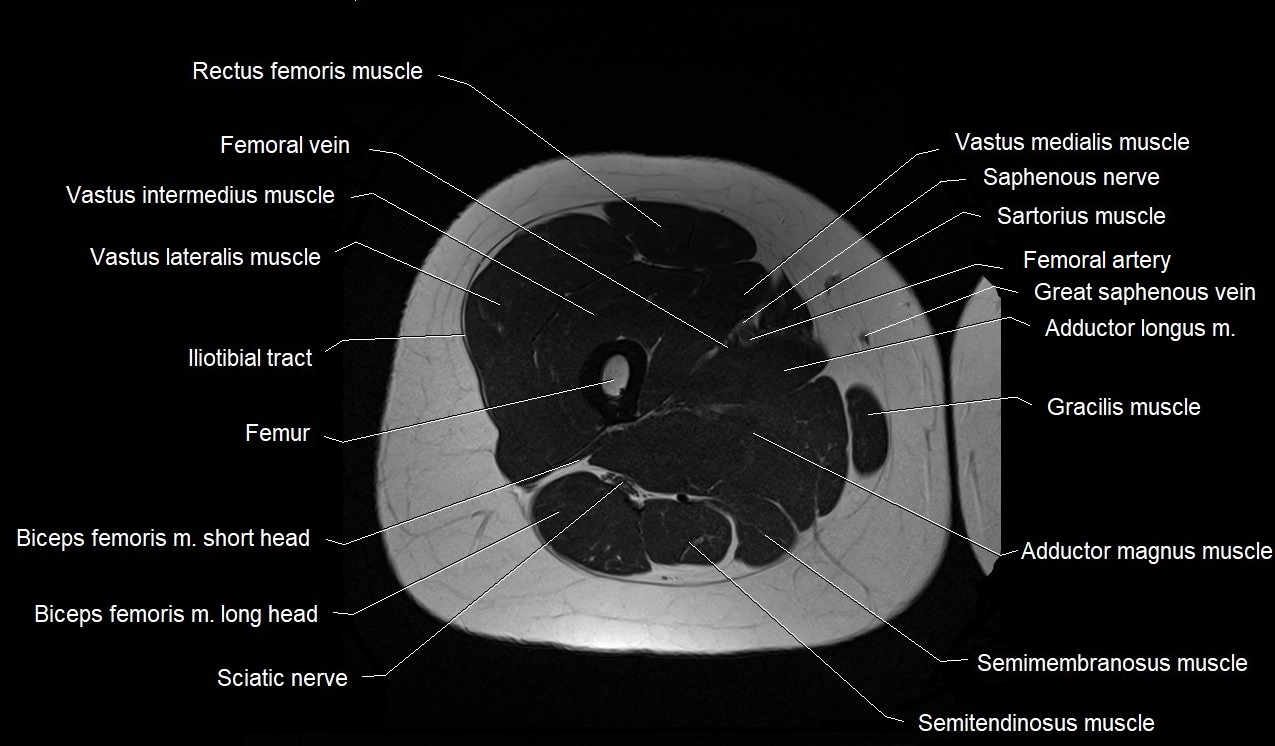

- Rectus femoris muscle

- Vastus intermedius muscle

- Vastus lateralis muscle

- Vastus medialis muscle

- Femur

- Iliotibial tract

- Biceps femoris muscle (Long head)

- Biceps femoris muscle (Short head)

- Semimembranosus muscle

- Semitendinosus muscle

- Gracilis muscle

- Adductor longus muscle

- Adductor magnus muscle

- Femoral artery

- Femoral vein

- Saphenous nerve

- Sartorius muscle

- Tibial nerve